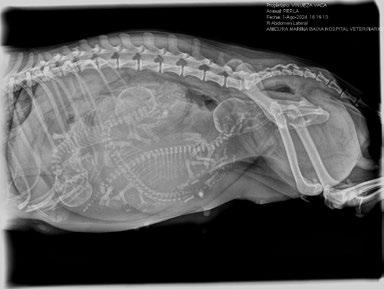

2. Radiografía de abdomen

El objetivo es valorar el tamaño y posición fetal y descartar obstrucciones en el canal del parto. También se puede contabilizar el número de fetos. Para ello, es más fiable contar el número de cabezas. Normalmente se visualiza mejor en una proyección VD. Figura 2.

Figura 2. RX de hembra gestante con medidas de cabeza y canal pélvico.